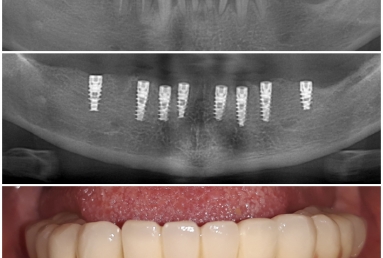

FULL ARCH FIX RESTORATION ON ALPHA BIO IMPLANTS

Our patient suffered from advanced periodontitis and we had to extract all mandibular teeth. After 2 month we inserted 8 Alpha Bio implants that healed in 4 months. All this time a full mobile temporary prosthesis was made, that was replaced in the end with fixed restorations made of porcelain fused to metal.